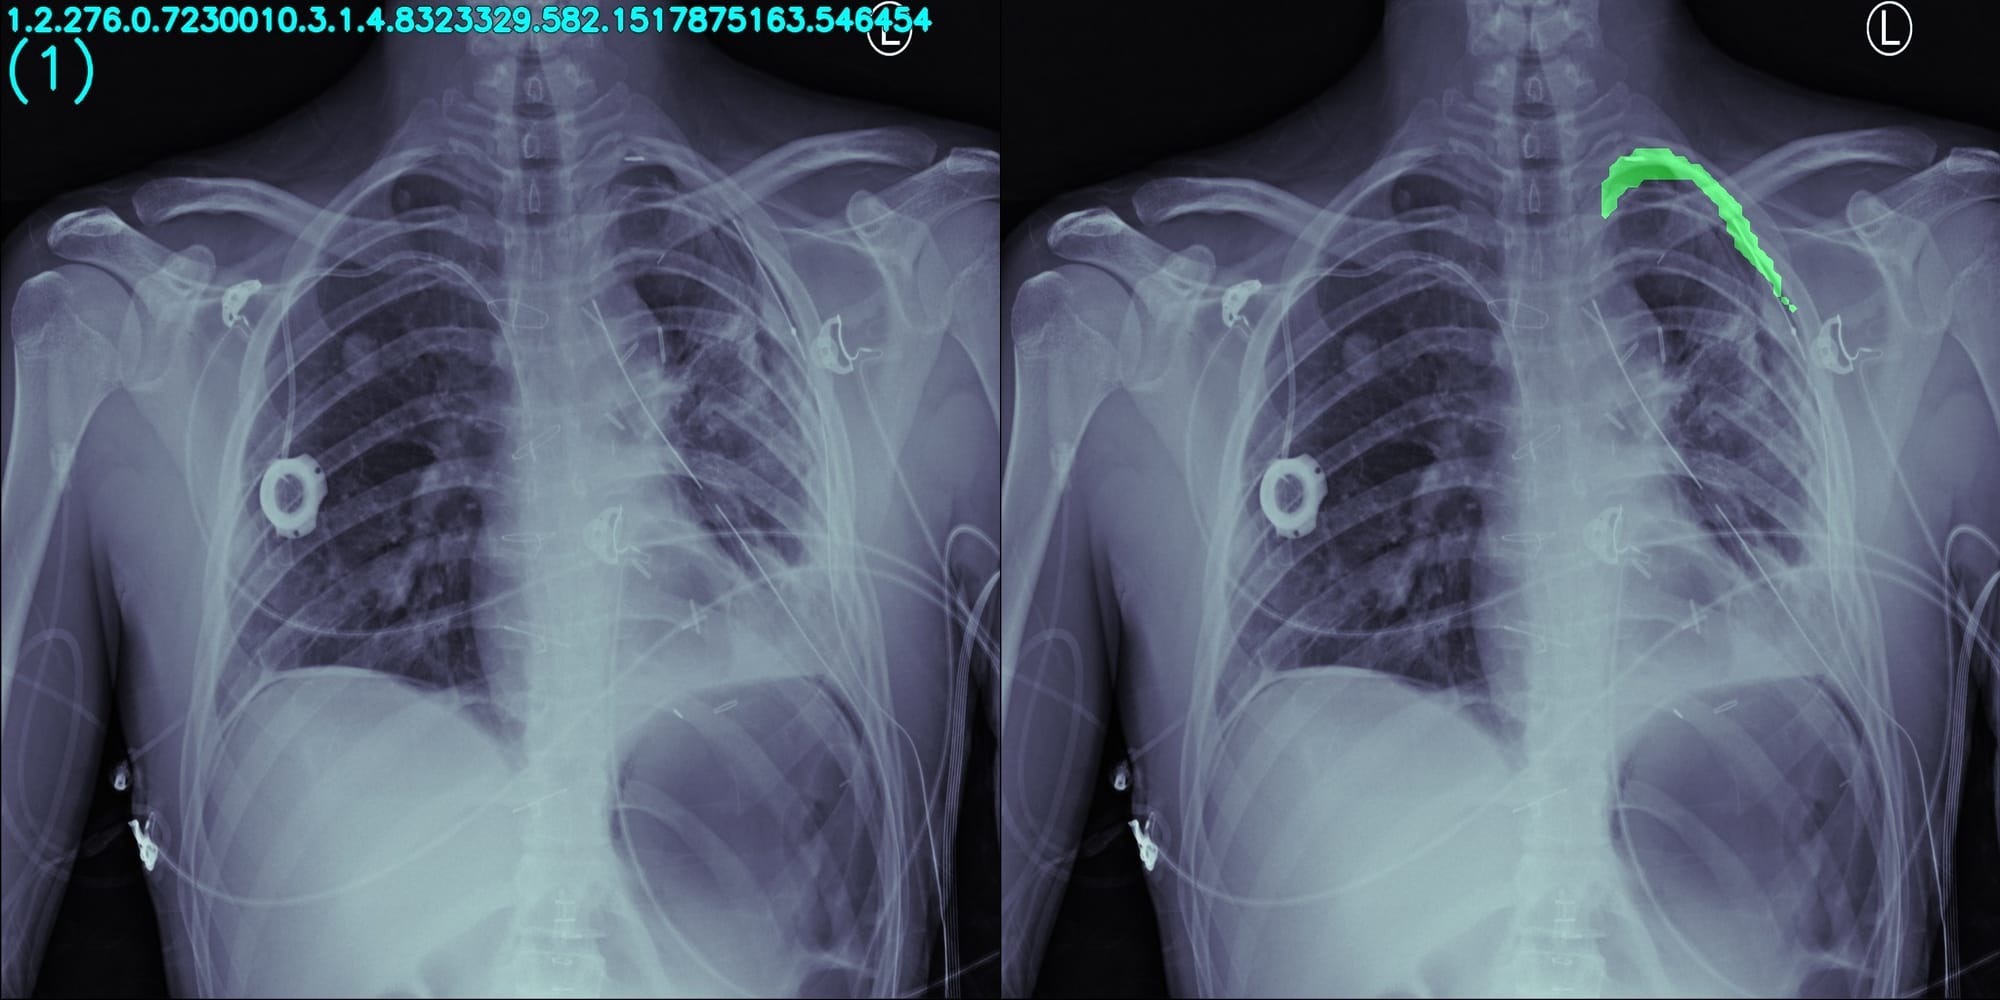

Segmentation of pneumothorax in a chest X-Ray image, by making use of Deep Transfer Learning and later analyzing segments to classify it as a positive and negative instance of pneumothorax presence. Currently UNet++ is used as core model with Dice-Coeff as evaluation metrics.